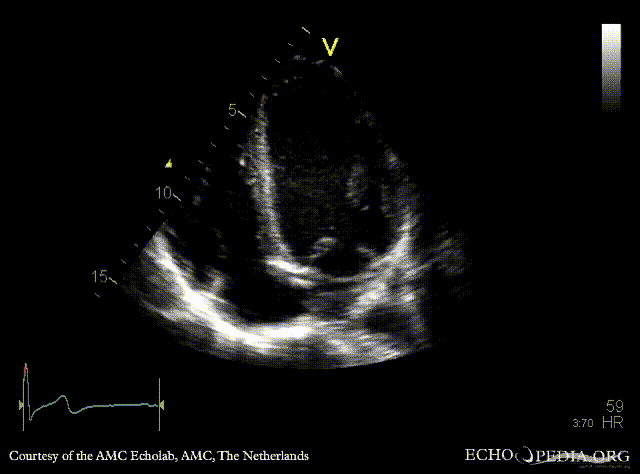

PSAX: Eustachian valve in right atrium, left coronary artery a vue PSAX: right coronary artery a vue